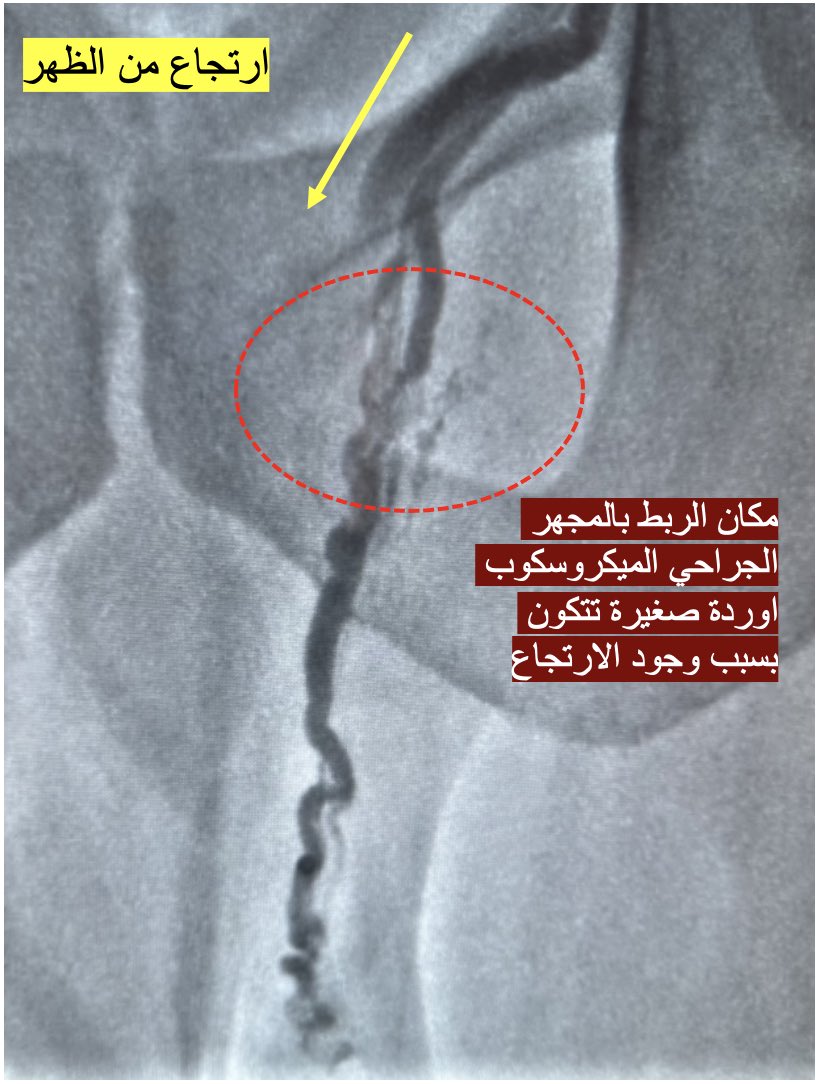

* لذلك عندما تعود الدوالي بعد الجراحة المجهرية اكثر فان الجميع متفق على تحويل المريض الى القسطرة (حتى القلة الذين تكلمنا عنهم ويذكرون معلومات مغلوطة - سنوضح ذلك لاحقاً)

١٥- ماذا عن رأي المجتمع الطبي الدولي؟ التوصيات التي عملت في عام ٢٠٢٣ وضمت اطباء عقم من جميع انحاء العالم - وعدة أطباء من السعودية بما فيهم الدكتور نايف الهذال - فقد اشادت بأمان علاج دوالي الخصية من ناحية انها تعمل بدون خطر اصابة الشرايين او تكوّن القيلة المائية. الجدير بالذكر ان التوصيات على طول صفحاتها وكلامها عن هجرة الحلقات (سنتحدث عنه) ولم تذكر الأشعة او خطرها مطلقاً.

١٦- ماذا عن القسطرة؟ جميع الآراء اتفقت انها غير متوفرة بكل مكان وأنها تحتاج لخبرة وتحدثت عن امكانية هجرة الحلقات.

لنوضحها: عند علاج الدوالي بالقسطرة فإن علاج الارتجاع بالظهر يكون اما باستخدام اللفائف المعدنية (الحلقات) او الصمغ الطبي (سنتحدث عنها وفروقاتها في ثريد اخر عن النتائج).